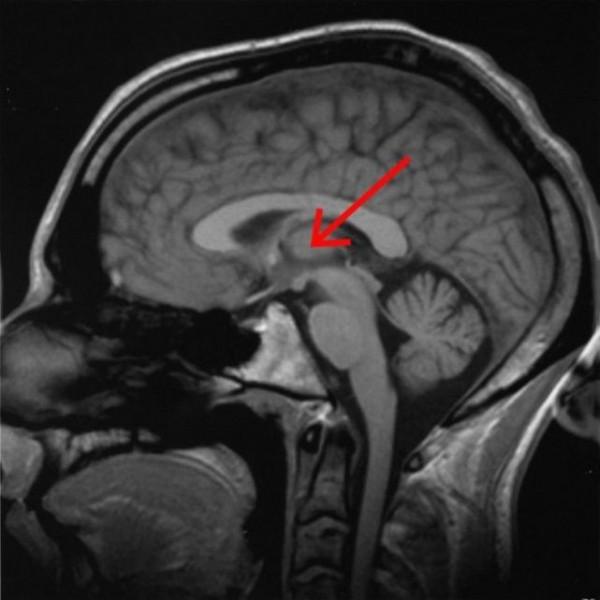

威斯康辛大學麥迪遜分校的研究人員發現,使用50 Hz電刺激中央外側丘腦時,處於麻醉狀態的獼猴能夠甦醒,並出現正常的清醒行為。 猴子睜開眼睛,生命體徵出現變化,面部和身體開始運動,並伸手去拿附近的物體。

不過,關閉電刺激之後,僅僅幾秒鐘,猴子便會再次閉上眼睛,回到無意識的狀態。 上述實驗,必須非常精準才能實現。 50 Hz的電脈衝,只能點選僅僅20奈米的特定位置。 這表明,中央外側丘腦對意識具有一定的啟動作用。 但這個實驗,是否可以證明,意識也如同運動、感覺、視覺等中樞皮層有著明顯的區域功能呢? 那倒是未必。

積水性無腦畸形兒童,是一種先天性疾病,通常表現為兩側大腦半球缺如(缺少大腦皮層),被薄襄所代替,裡面充滿腦脊液。除了大腦皮層之外,患兒的腦幹、小腦,腦膜健全,有的可能會殘存一定的顳葉、枕葉,或額葉。 這些兒童雖然往往早夭,但大多能表現出意識活動。 這足以說明,雖然大腦皮層對意識具有重要的決定作用,但大腦皮層也絕對不是意識產生的必須條件。